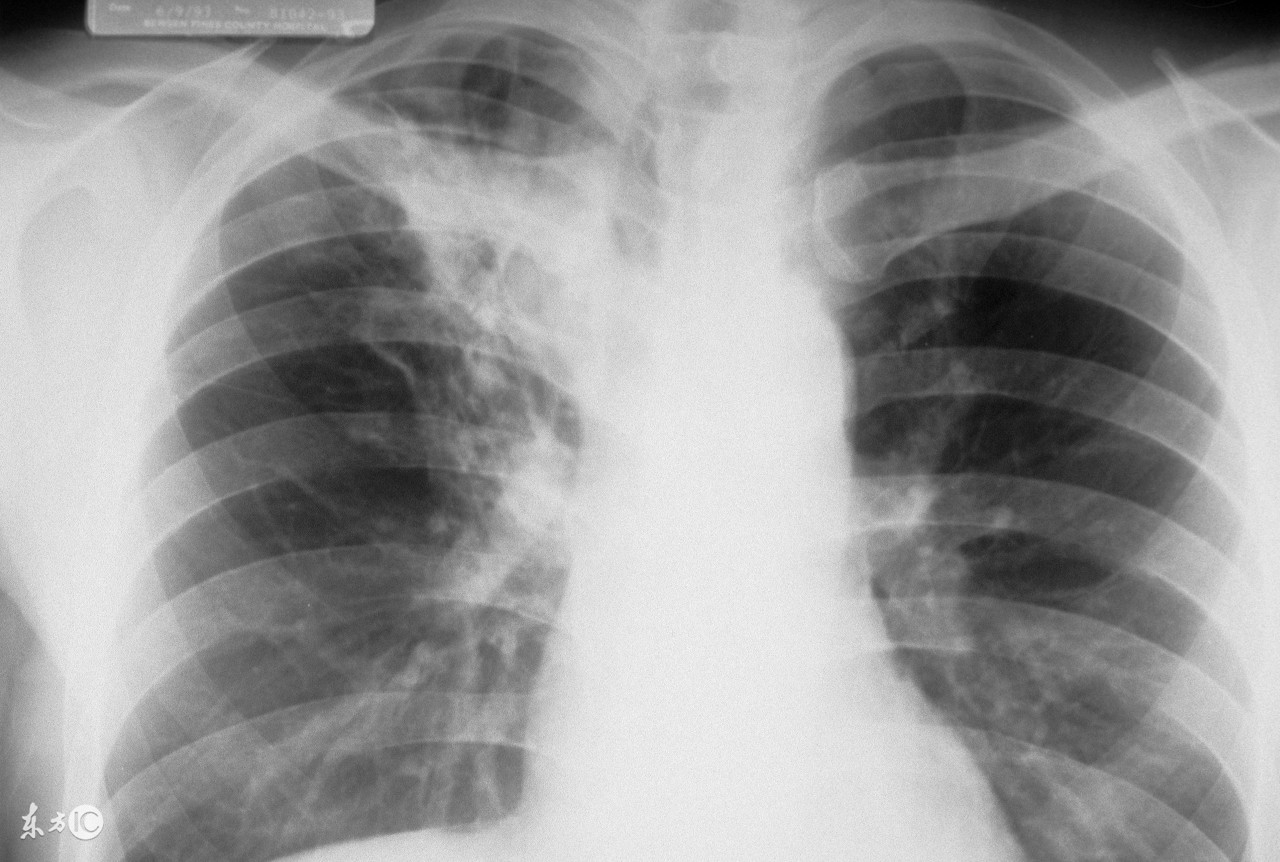

为了更准确的诊断肺结核,一般都要做肺结核皮试,通过做这个检查可以明确人体带菌的概率,肺结核皮试出现双圈是什么意思?阳性和阴性有什么不同?

肺结核皮试结果判断中,如果皮肤出现双圈,是强阳性的表现。现在向大家介绍一下皮试的具体情况。

肺结核皮试以皮肤做皮试的部分出现硬结大小作为判断反应的标准:

(1)阴性:注射部位无硬结或硬结平均直径<5mm。第一次的皮试液浓度为0.1毫升含1个单位的结核菌素,注射后48小时由主管医生看结果;如果为阴性则再做第2次,皮试液浓度为0.1毫升含5个单位结核菌素,再过48小时看结果。如果两次试验均为阴性,才能确定为阴性。

(2)阳性:硬结平均直径≥5mm。5-9mm为一般阳性;10-19mm为中度阳性;≥20mm(儿童≥15mm)为强阳性;如果直径<20mm但有水泡,坏死,双圈,淋巴管炎等均为强阳性。

结核病皮试如何判断PPD阳性的临床意义:

1、PPD皮试阳性表示对结核杆菌具有敏感性,反应越强,受到结核菌感染的可能性越大。通常直径>15mm或有水泡,认为是新近受到感染。但皮试阳性并不意味着就是结核病人。因为初次感染结核菌后自然愈复的倾向很大,临床发病者只占初染者的5%--10%。更不意味着PPD皮试阳性者就具有传染性。因此幼儿园拒绝PPD皮试阳性幼儿入园是错误的。

2、感染结核菌或接种卡介苗后PPD皮试阳性,随着时间推移,阳性反应会随之减弱。但此过程须时数年。通常认为接种卡介苗3个月以上,硬结直径5—9mm为接种阳性。30个月以内硬结直径须在20mm以上才考虑为自然感染。30个月以上硬结直径10—19mm以上考虑为自然感染结核菌。